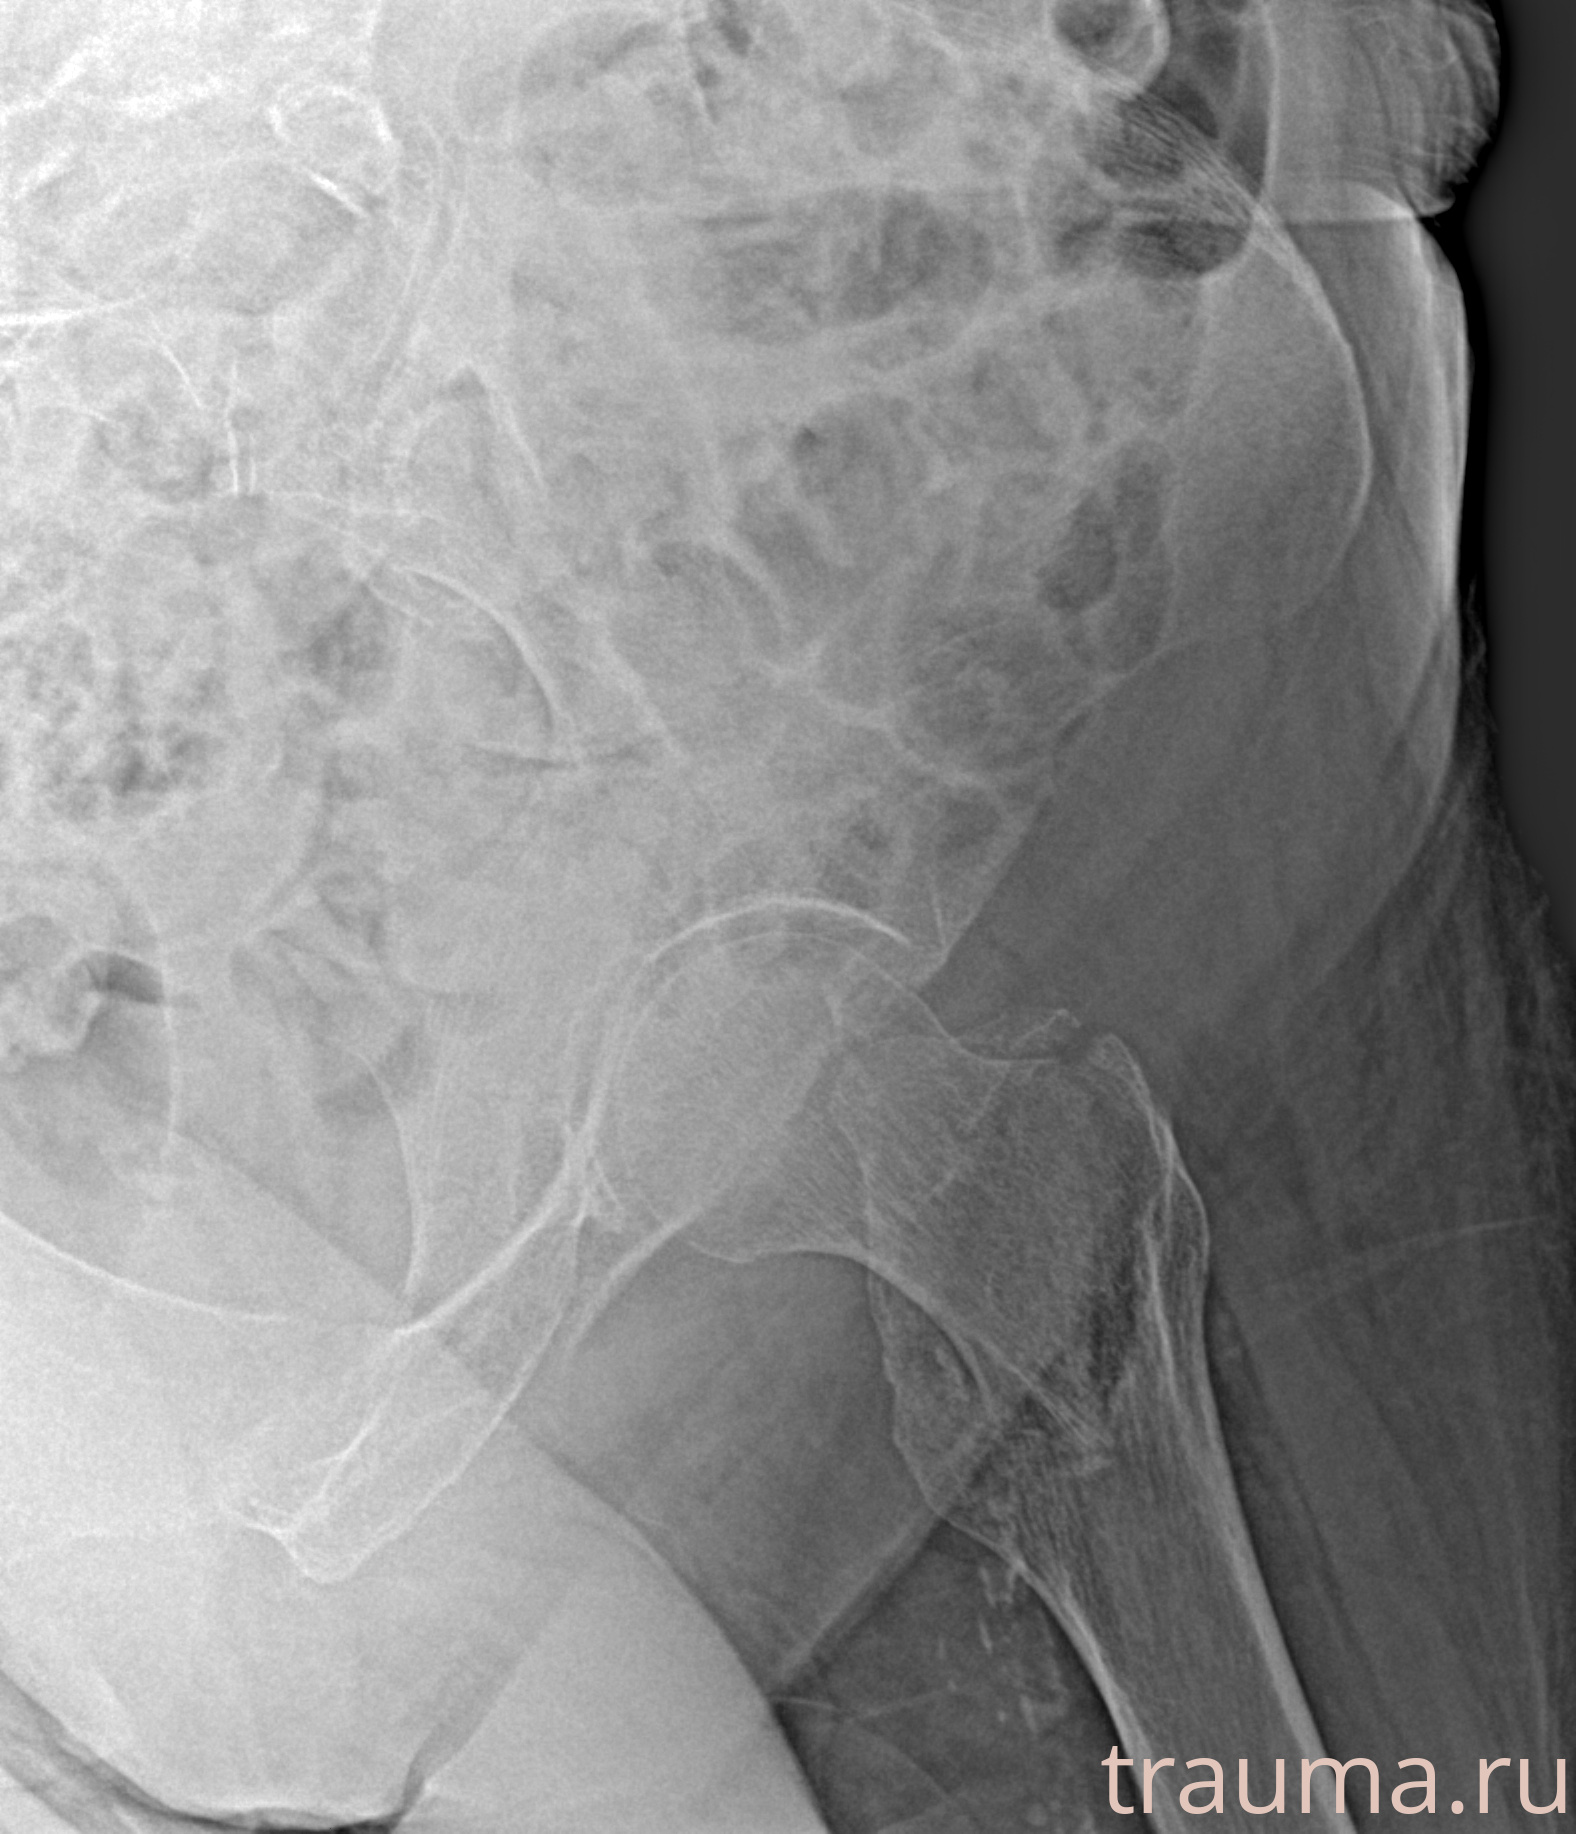

Рентгенограммы

Рентген на дому: по вашему адресу приезжает врач-рентгенолог, травматолог-ортопед с мобильным рентгеновским аппаратом, проводит диагностику травмы или заболевания, делает необходимые рентгенограммы, дает рекомендации по дальнейшему лечению. Получить качественные снимки в домашних условиях возможно благодаря уникальной методике, разработанной МосРентген Центром для института  Склифосовского

при переломе шейки бедра и пневмонии от компании МосРентген Центр - партнера Института имени Склифосовского